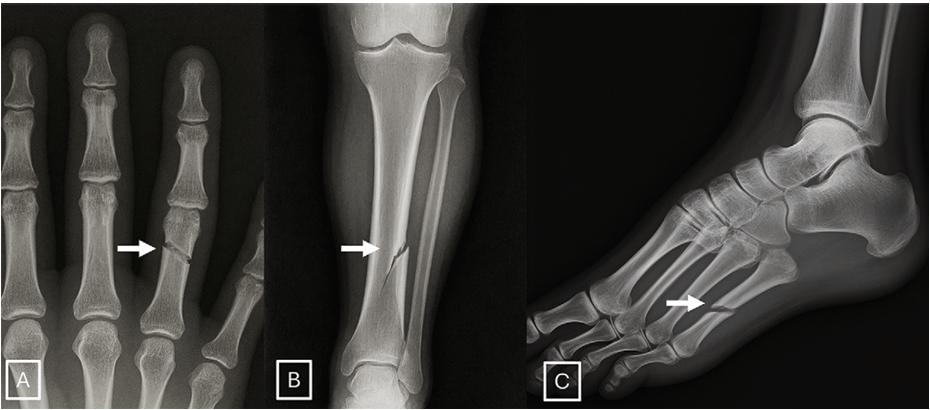

그렇다면 전문가들은 어떤 단서를 통해 합성 이미지를 판별해 낼 수 있었을까? 설문 결과에 따르면 인공지능이 생성한 X선 이미지에는 몇 가지 공통적인 특징이 있었다. 예를 들어 뼈 표면이 지나치게 매끄럽고 조직의 질감이 균일하며 노이즈 패턴이 너무 일정한 경우가 많았다. 또한 척추가 지나치게 완벽한 대칭을 이루거나 골절선이 실제보다 훨씬 깔끔하게 나타나는 경우도 있었다. 쉽게 말해, 너무 완벽한 이미지가 오히려 가짜일 가능성을 높였던 것이다.